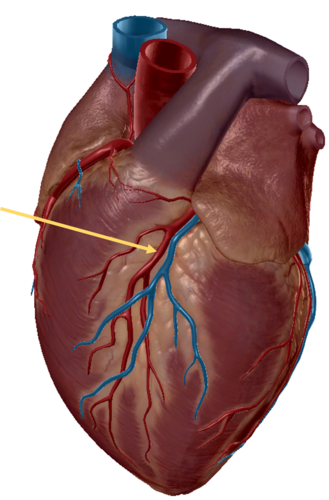

anterior inter ventricular sulcus

right coronary artery

circumflex artery

great cardiac vein

anterior inter ventricular artery

left pulmonary veins

left pulmonary artery